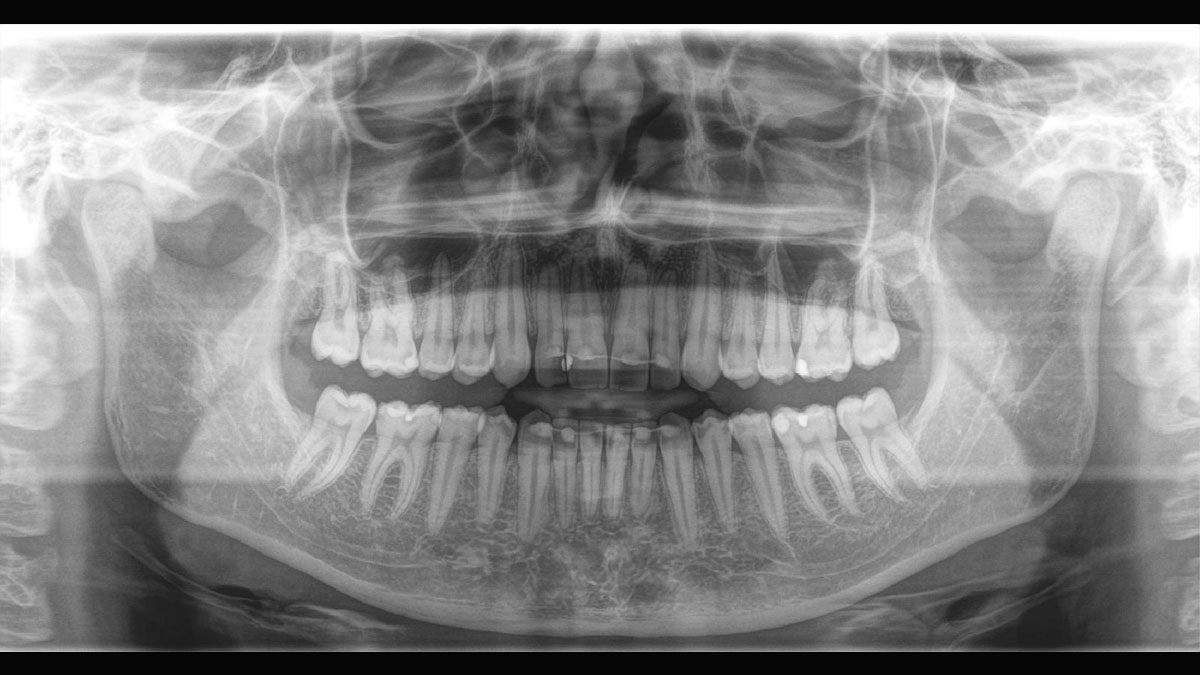

Der Autofokus erzeugt aus mehreren tausend Einzelbildern automatisch eine beeindruckende scharfe Panorama-Röntgenaufnahme

Eine Röntgenaufnahme muss sofort diagnostizierbar sein. Der Autofokus hilft dabei erheblich. Orthophos SL erfasst mehrere tausend Einzelbilder in einem Zyklus und erkennt automatisch scharfe Bereiche, um ein gleichmäßig scharfes Gesamtbild zu erzeugen. Der intelligente Autofokus erfordert keine manuellen Arbeitsschritte vor und nach der Erfassung.